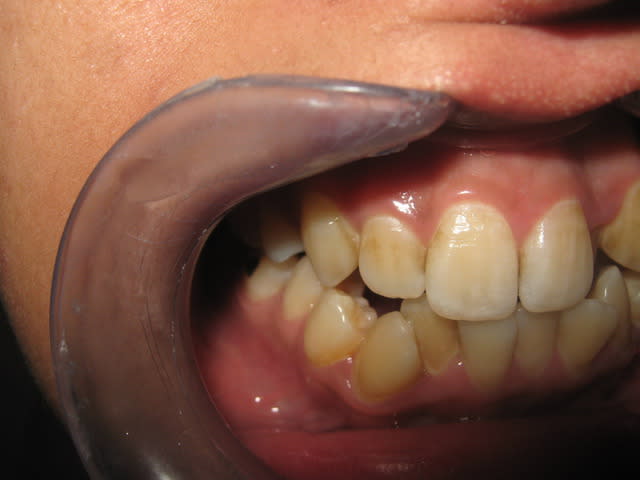

je viens de recevoir un cas d'orthodontie un peu copmliqué et je veux vos suggessions merci

patiente age 26 ans

profil hyperdivergent

la 24 est absente

vous trouvez ci joint les photos